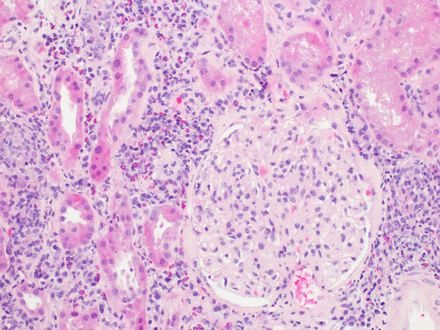

#Granulomatous interstitial#nephritis by Shah S. et al http://ow.ly/TLie8#openaccesspic.twitter.com/Bu4thwLxkA

-